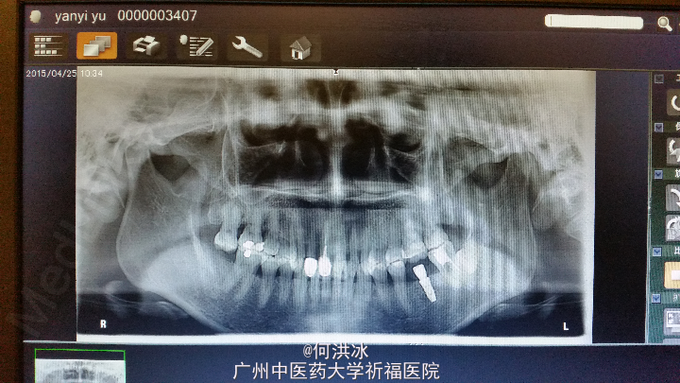

口腔查见36缺失,35、37为固位体双端固定桥修复,暂无松动。37咬合面破损,探尚无继发龋坏。36桥体龈方有大量食物嵌塞,牙龈充血、红肿明显。全景片示两侧基牙,35未做根管治疗,37已做根管治疗,二牙根尖区无阴影。36失牙区可利用骨高度近12mm,尚致密,无缺损影。

1,局麻下拆除原固定桥,局部超声龈上法治、龈下刮治,非常完善的前期牙周处理。 2,一个月后手术。植入Dentium 4.5*10植体一枚。术后全景片示角度、方向非常理想。